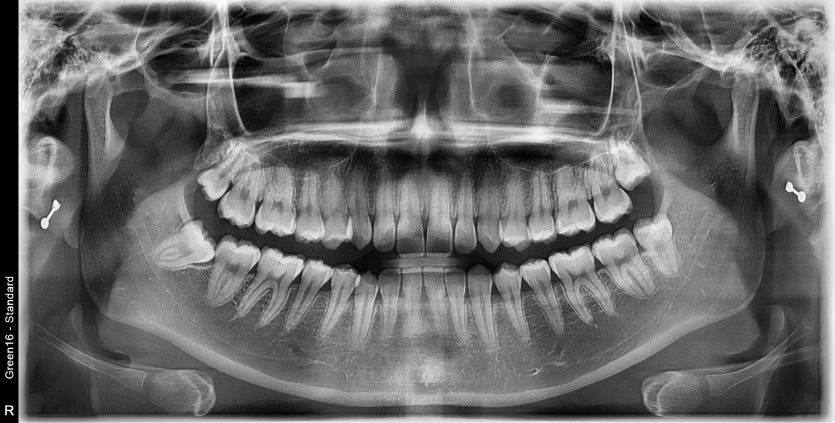

#38 사랑니 발치

구강 외과 전문의가 당일 발치했습니다.